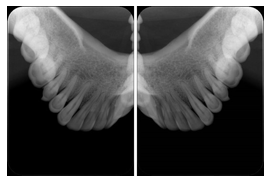

2 Occlusal Vertical Maxilla A Dental Image Layout

DL-C001A

Reference: DL-C001-U1L0

Reference: DL-C001-U2L0

2 Occlusal Vertical Mandible A Dental Image Layout

DL-C002A

Reference: DL-C002-U0L1

Reference: DL-C002A-U0L2

2 Occlusal Horizontal Maxilla A Dental Image Layout

DL-C003A

Reference: DL-C003-U1L0

Reference: DL-C003-U2L0

2 Occlusal Horizontal Mandible A Dental Image Layout

DL-C004A

Reference: DL-C004-U0L1

Reference: DL-C004-U0L2